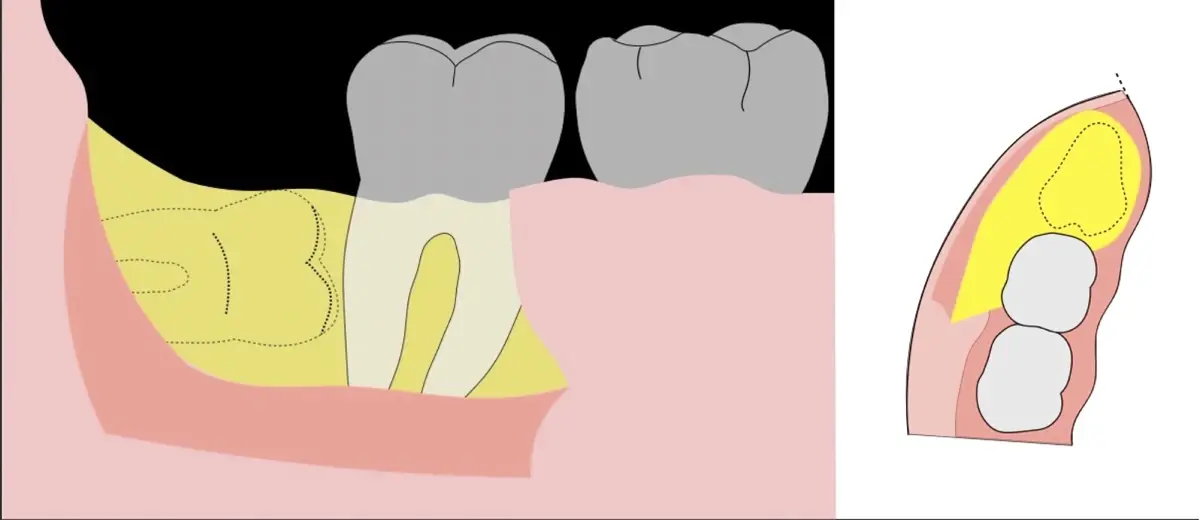

Es imprescindible conocer la ubicación de la tercera molar. Se puede emplear, adicionalmente a la evaluación clínica, herramientas radiográficas (panorámica y periapical) y tomográficas (Cone beam) para determinar la posición, grado de retención y proximidad a estructuras vecinas de riesgo como el nervio dentario inferior y así evitar lesiones (Figura 1).